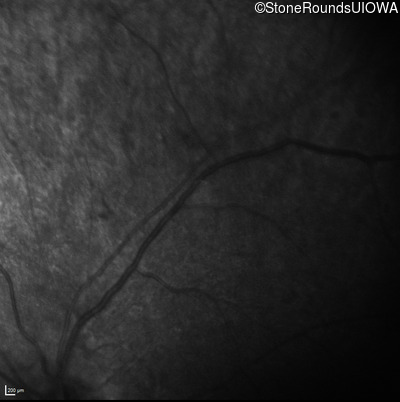

Infrared Fundus Photograph - Right - No Light Perception

Exemplar